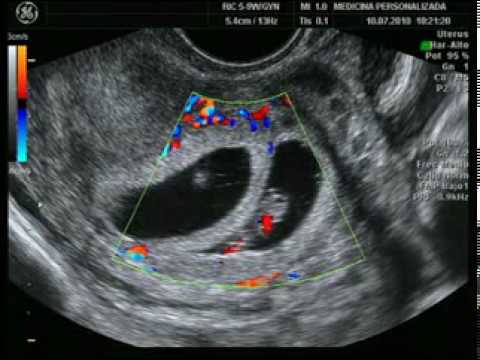

Primerizos con Mellizos!!: Ecografía de las 12 semanas